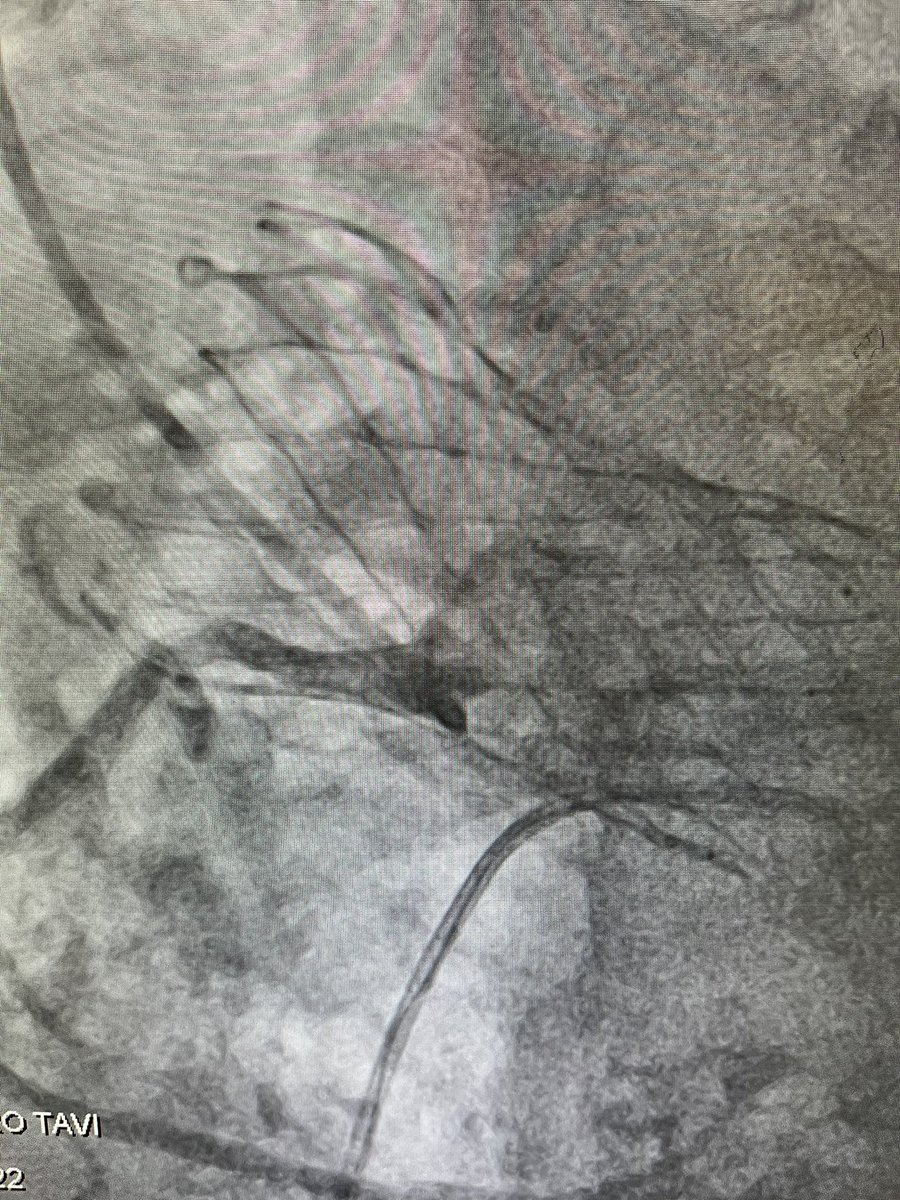

Evolut Fx Plus has arrived! Large windows for coronary access. Watch the first case recorded live on OPCI.live this Saturday St. Francis Hospital & Heart Center OPCI Ziad Ali David J. Cohen, MD, MSc #richierich

Case highlights: Commissural alignment, cusp overlap, horizontal aorta, selective coronary angiography and freedom of catheter manipulation through enlarged cells. And cameo by Rich Shlofmitz. David J. Cohen, MD, MSc Omar Khalique St. Francis Hospital & Heart Center Billal Tokhi Ziad Ali